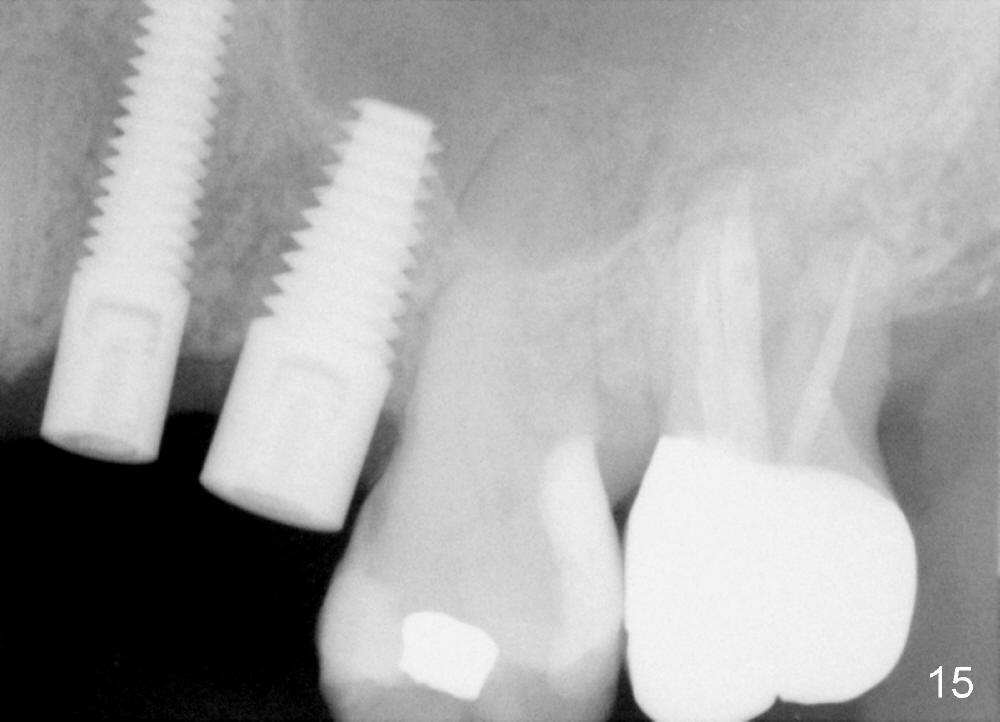

Three month follow-up shows that the gingiva and bone heal around these two implants (Fig.13-15). Crowns are cemented 4.5 months postop (Fig.16). There is no or minimal bone loss 9 months post cementation (Fig.17, as compared to Fig.15). The bone is stable around the implants 18 months post cementation (Fig.18 panoramus). Root canal therapy is done at #14 between the last follow up appointments.